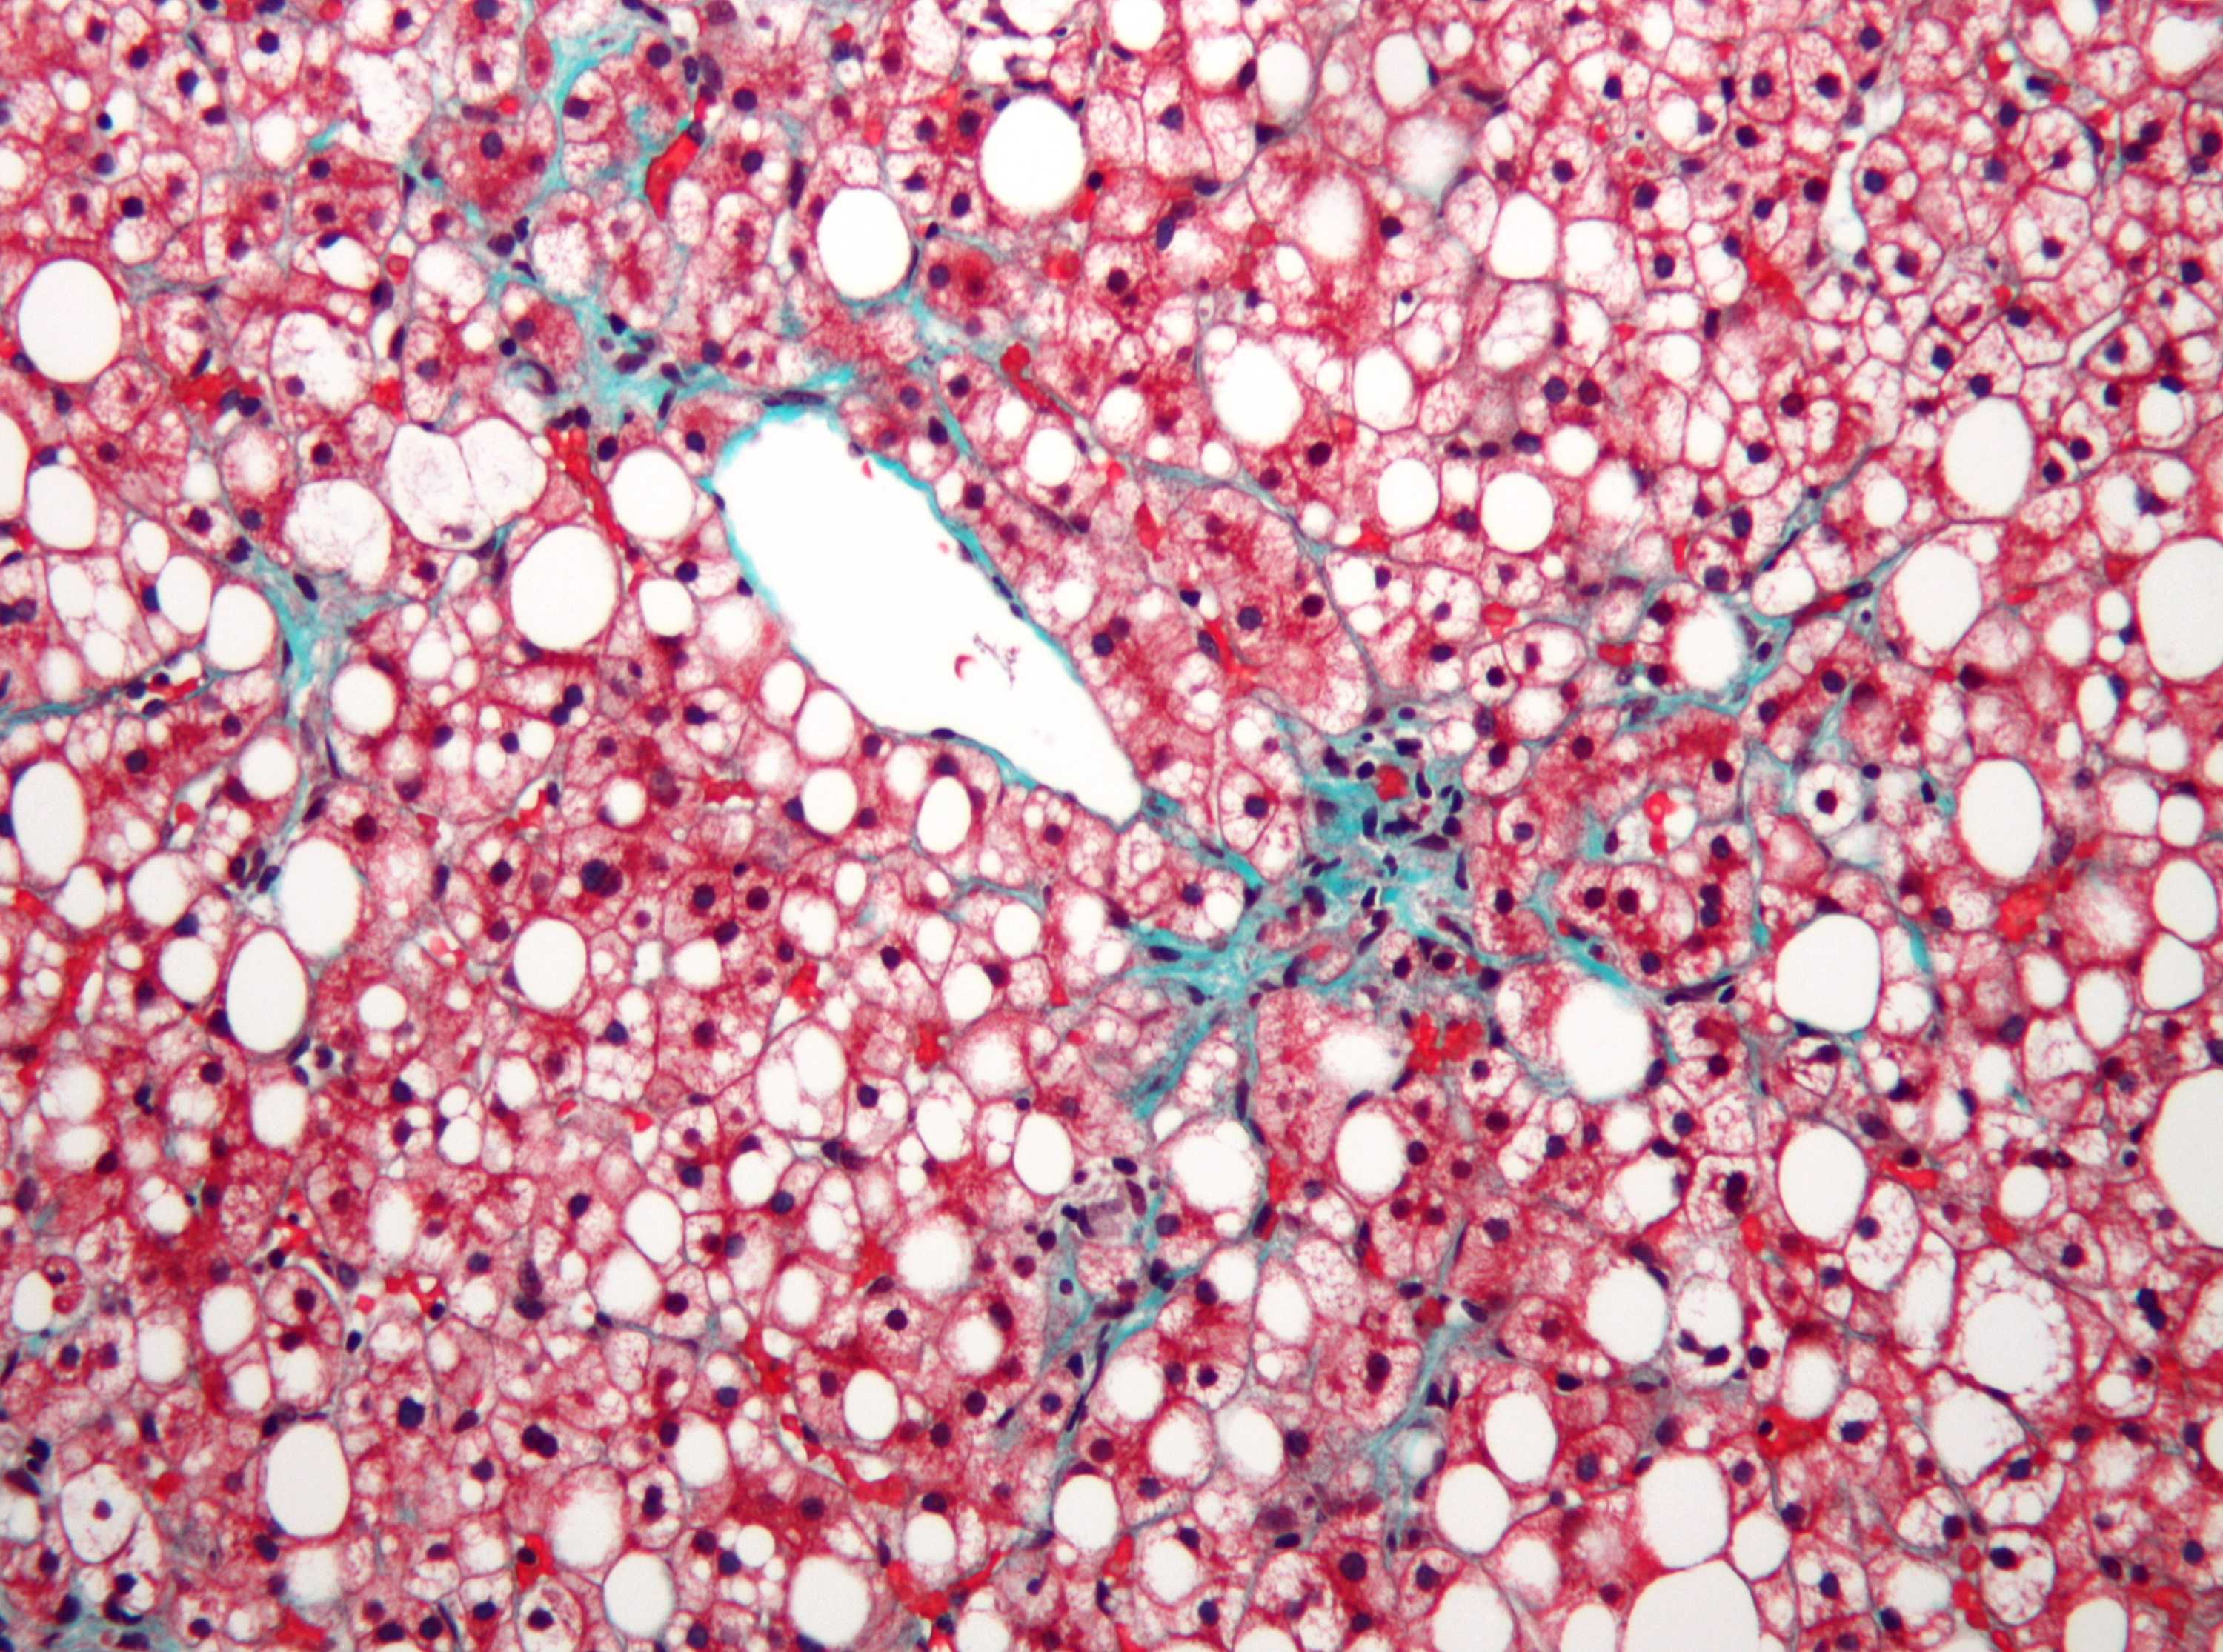

Micrografía de enfermedad del hígado graso no alcohólico.

Si se acumula demasiada grasa en el hígado, puede dañar el órgano. (Wikimedia Commons: Nefrona (CC-BY-SA-3.0))